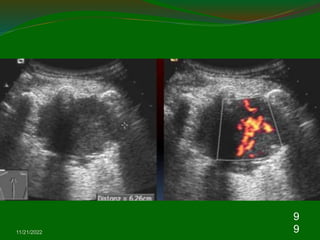

Chest US with color Doppler is a powerful tool for

empyema .

The empyema can be detected by chest US with an

image of a hypoechoic lesion with complex-septated

Color Doppler ultra‐ sound could not identify vessel

signals in pericavitary atelectasis.

The lung abscess in the US image reveals hypoechoic

lesion with typical pulmonary consolidation, irregular wall

Color Doppler ultrasound could identify vessel signals in

pericavitary consolidation